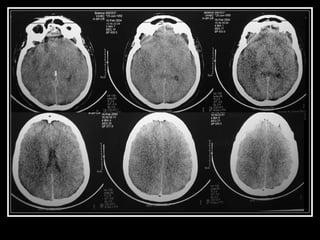

Exames de Imagem Qual a primeira escolha na emergência? Por quê? Qual o método mais sensível?

Exames de ImagemQual a primeira escolha na emergência? Por quê? Qual o método mais sensível?